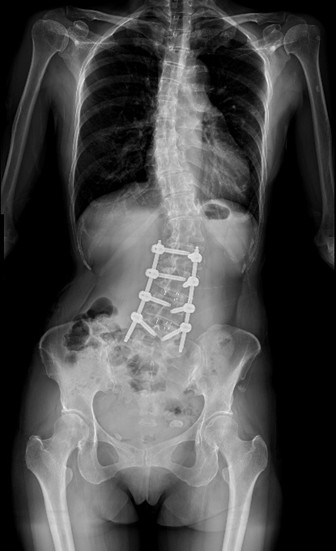

【記者張原銘、張皓傑台中報導】55歲的黃小姐年輕時即被健檢醫師提醒有脊椎側彎,但多年來未加以治療。近兩年症狀明顯惡化,出現劇烈腰背疼痛、下肢麻痺與腫脹,夜間常因疼痛難以入眠,甚至影響行走能力與工作生活品質。經友人推薦,黃小姐前往臺中市立老人復健綜合醫院(簡稱中醫大市醫)骨科就醫,經微創脊椎中心助理副院長張建鈞醫師評估後,決定接受3D導航微創脊椎矯正手術。術後脊椎側彎角度由47度矯正至10度,身高增加約5公分,困擾長達25年的病痛大幅改善,終於能安穩入睡。

張建鈞醫師指出,患者因長期未治療,脊椎側彎角度已達48度,屬於中重度退化性脊椎側彎,且合併二尖瓣膜脫垂的心臟病史,若採傳統開放式手術,手術風險相當高。經完整影像評估與跨科討論後,醫療團隊建議採用「微創前開3D導航矯正手術」,由身體側邊的小切口進行矯正與支撐重建,在不大幅破壞背部肌群的情況下完成手術,有效降低出血量與併發症風險。術後恢復快速,約4至5天即可出院,疼痛亦明顯減輕。黃小姐笑說,術後穿著背架反而帶來前所未有的安全感,甚至捨不得太快卸除。

張建鈞醫師進一步分析,此次困難手術能順利完成,關鍵有三大因素。第一,術中導入O-arm 3D即時影像結合S8電腦導航系統,如同為脊椎手術加裝GPS,可即時掌握椎體位置,精準植入鋼釘;第二,採用微創前開方式,從身體側邊開設微小切口,避免破壞背部重要肌肉與結構,大幅降低出血與神經血管傷害風險;第三,由微創脊椎中心跨專科團隊合作,首創由三位脊椎專科主治醫師偕同執行脊椎側彎矯正手術,從術前評估、手術執行到術後照護皆採標準化流程,確保手術安全與品質。